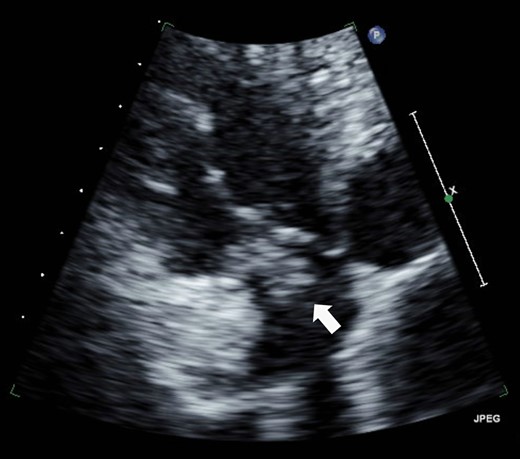

Eight years ago, a DDD pacemaker was implanted in an elderly man due to complete atrioventricular (AV) block. The pacing sites were the appendage of the right atrium and the apex of the right ventricle (Fig. 1) subsequently he suffered PICM with an LV ejection fraction of 37% and obvious dyssynchrony. He had chronic heart failure of NYHA II. Suddenly, the patient developed fever and complained of difficulty eating. Transthoracic echocardiography showed a vegetation (11 × 12 mm2) at the pacemaker leads, and this vegetation was also attached at the tricuspid valve (Fig. 2). Laboratory examination showed elevated white blood cell count and C reactive protein levels. He was diagnosed with PAIE, although the peripheral blood cultures showed no bacteria. After antibiotic therapy, laboratory examination showed decreasing inflammation parameters, but the size of the vegetation remained stable.

A vegetation on the tricuspid valve (arrow). Transthoracic echocardiography shows a vegetation (11 × 12 mm2) attached at the tricuspid valve.